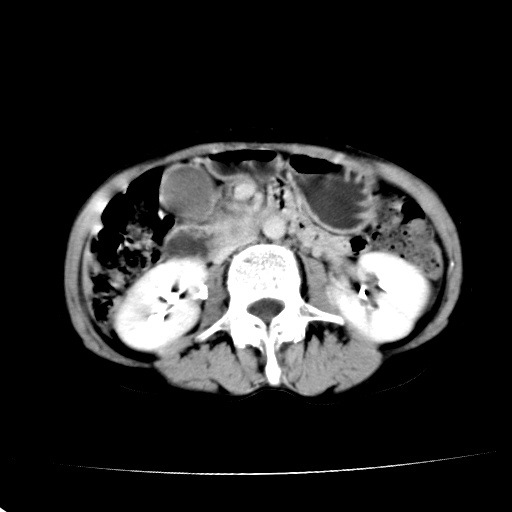

以下是引用jiangjing在2008-6-3 13:36:00的发言:[br]支持 胰头癌------肝内外胆管扩张,胰管扩张,胰头增大,增强见结节状轻度强化影,双管征明显

以下是引用卜一在2008-6-3 14:40:00的发言:[br]支持:胰头癌!(肝内外胆管扩张,胆囊高度扩张,胰管扩张,胰头增大,增强见结节状强化,明显低于胰腺强化密度,并明显见双管征)

以下是引用dyqct在2008-6-3 14:54:00的发言:[br]支持 胰头癌伴肝内外胆管扩张,胰管扩张,胰头增大,增强见结节状轻度强化影,双管征明显。肠系膜上静脉已受侵(已不能手术),建议离子植入治疗吧。